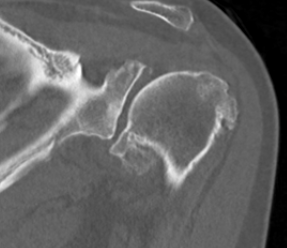

Type A2 Type B1

Type B2 Type B3

Type B3